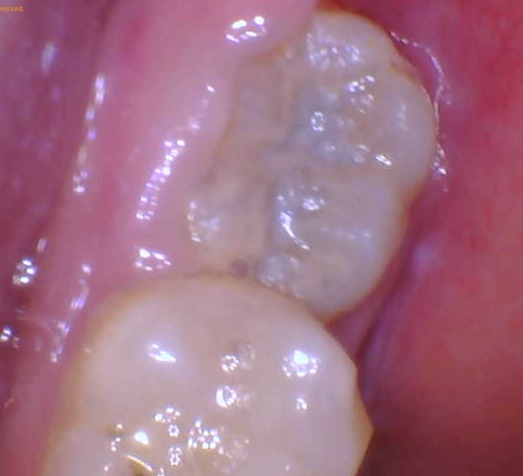

Pictures of wisdom teeth with plaque

Real picture of a wisdom tooth with plaque covering all over it:

This is a picture of a wisdom tooth with plaque AND a cavity.